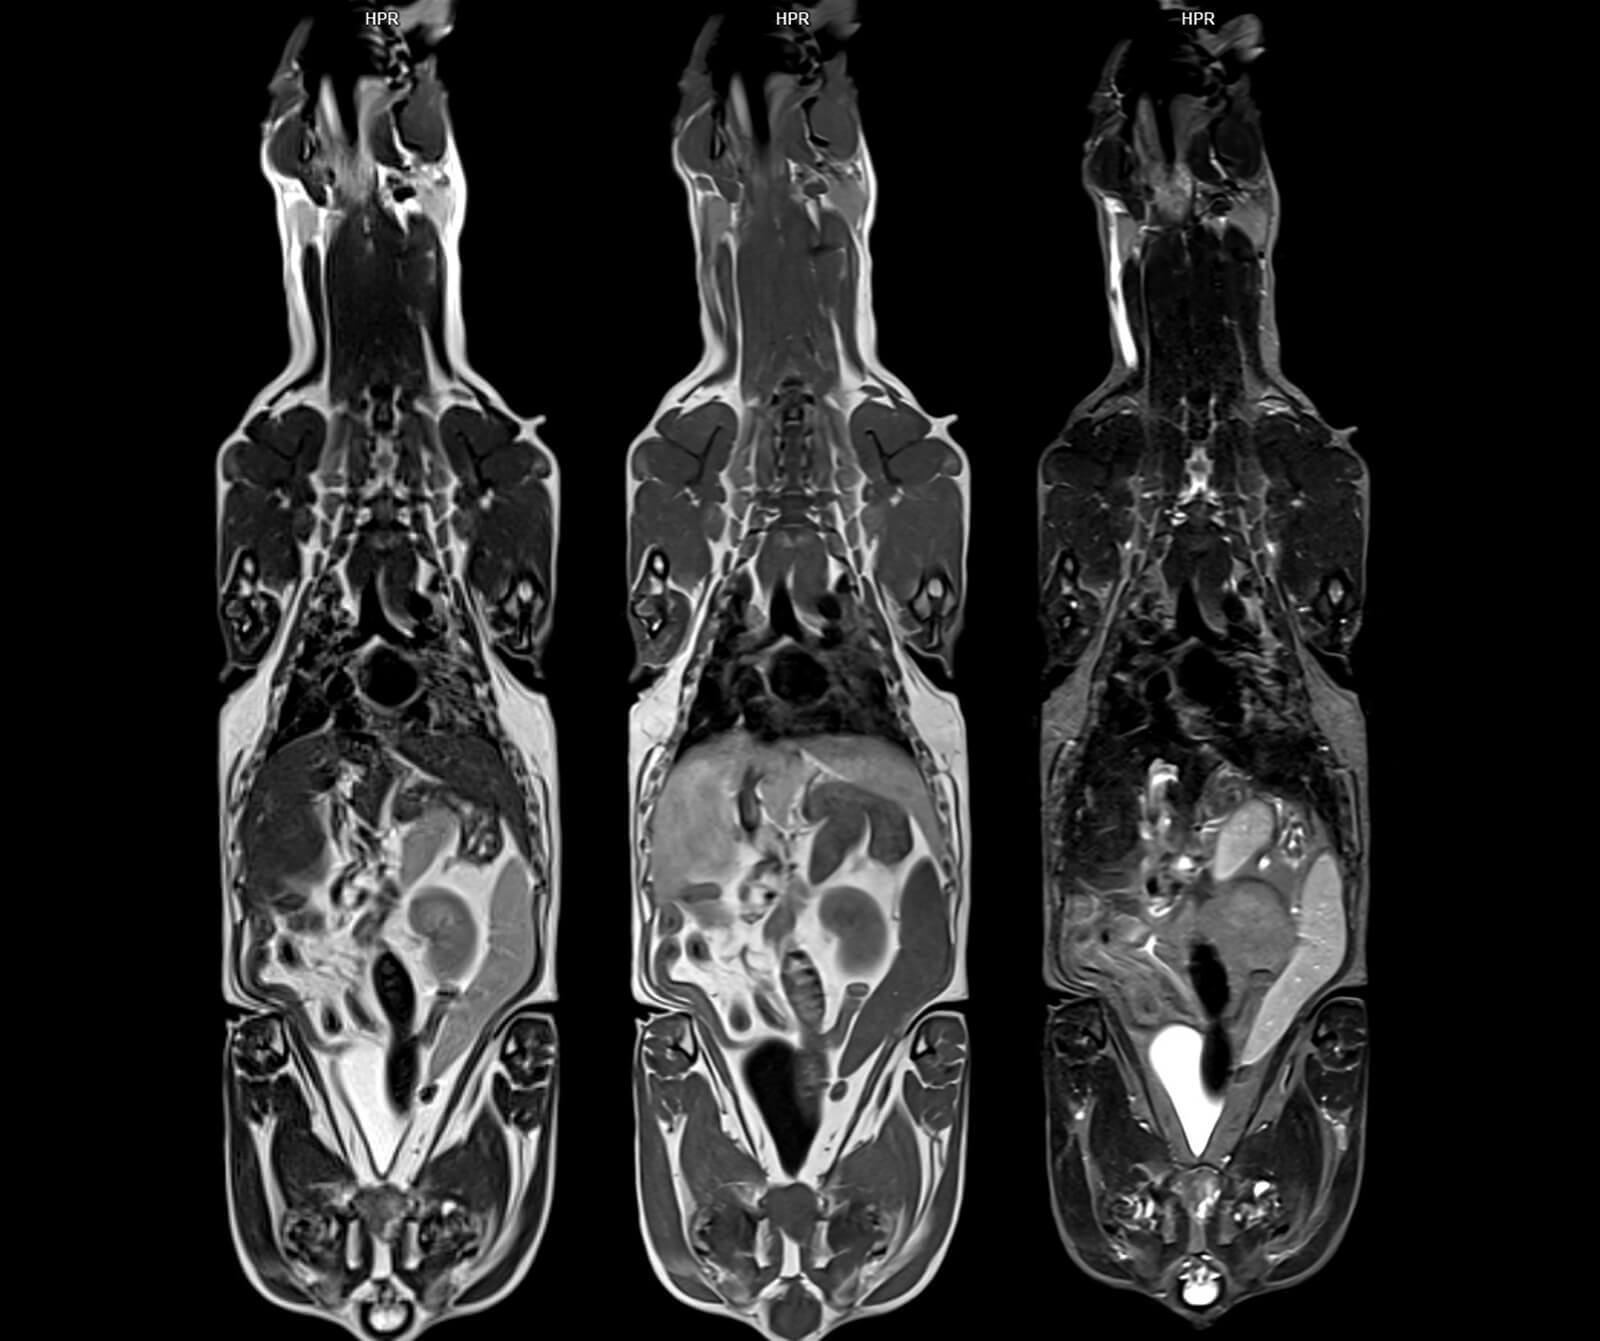

• Yumuşak doku ve organ tümörleri

• Kanser evrelemesi ve tedaviye yanıtın takibi

• Özellikle beyin, karaciğer, pankreas, meme ve prostat tümörleri

Bu teknolojik altyapı sayesinde geniş görüntüleme alanlarında dahi yüksek çözünürlük ve detaylı kesitsel görüntüler sağlanırken, sevimli dostlarımızın anestezi altında geçirdiği süre optimum düzeyde tutulur ve tanısal doğruluk en üst seviyeye çıkarılır.

Veteriner hekimlik amaçlı kullanım için optimize edilmiş bu sistemler ile gerçekleştirilen görüntüleme incelemeleri Veteriner Manyetik Rezonans (Veteriner MR) olarak adlandırılmaktadır.